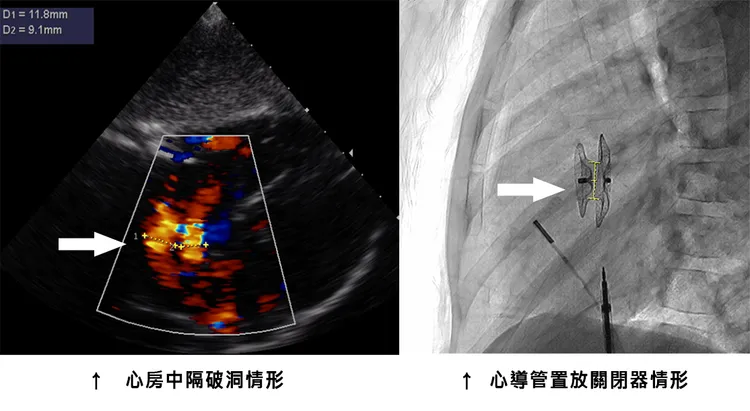

這位女童在國小新生心電圖檢查中被發現心軸異常,之後被轉介到澄清醫院進一步檢查。超音波檢查顯示她的左心房和右心房之間有兩個破洞,分別為0.9公分和1.2公分,這兩個破洞之間的距離只有0.4公分,同時右心房和右心室也有擴大的情況。這讓女童的家長感到困惑,因為女童沒有任何明顯的症狀,只是不太愛運動。

對於這位女童的心房中隔破洞,何季麟主任進行了心導管手術。他通過鼠蹊部股靜脈進入女童的心臟,使用心房中隔缺損關閉器將破洞封住。由於女童的兩個破洞相距僅0.4公分,所以可以一次性封住兩個破洞。這個關閉器是由鎳鈦合金製成的,能夠緊密地封閉心房中隔,隨著女童的心臟成長,關閉器也會跟著正常發展。這意味著女童不需要將關閉器取出,可以一輩子留在心臟內。